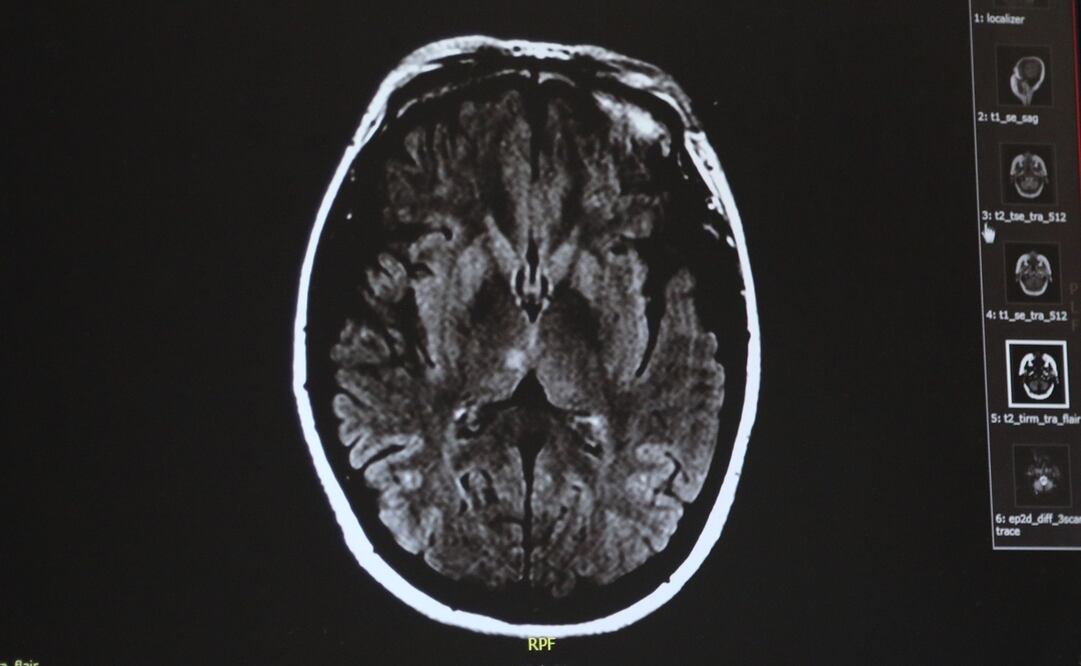

El estudio publicado en “ Journal of Neuroscience ” se basó en una metodología de tipo neuronal, a través de la aplicación de resonancia magnética en 18 voluntarios en siete mujeres y 11 hombres, a los que se les solicitó que diferenciaran entre la duración de tiempo de un estímulo visual de extensión variable y otro de tipo auditivo con perdurabilidad fija.

“Para investigar la base neuronal del tiempo subjetivo, realizamos un estudio de resonancia magnética funcional utilizando un procedimiento de adaptación que nos permitió manipular la duración percibida manteniendo constante la duración física”, explicaron los autores del trabajo, Masamichi J. Hayashi y Richard B. Ivry.

Con el estudio se obtuvo una visible evidencia fisiológica en torno a la codificación de una población de neuronas en la corteza parietal derecha de nuestro cerebro, la cual sería la encargada de reflejar nuestra experiencia subjetiva sobre la duración del paso del tiempo.

Este grupo específico de neuronas se ubican en el “giro supramargnial” (SMG) del cerebro, que conforma la parte inferior del lóbulo parietal. El SMG está asociado a la interpretación del lenguaje y procesos cognitivos superiores, como la lectura o escritura, la memoria de trabajo y el aprendizaje, mientras que el lóbulo parietal funciona como un regulador del sentido espacial, es decir la forma en que se ubica un objeto en el espacio.

Foto: Hayashi e Ivry, JNeurosci 2020